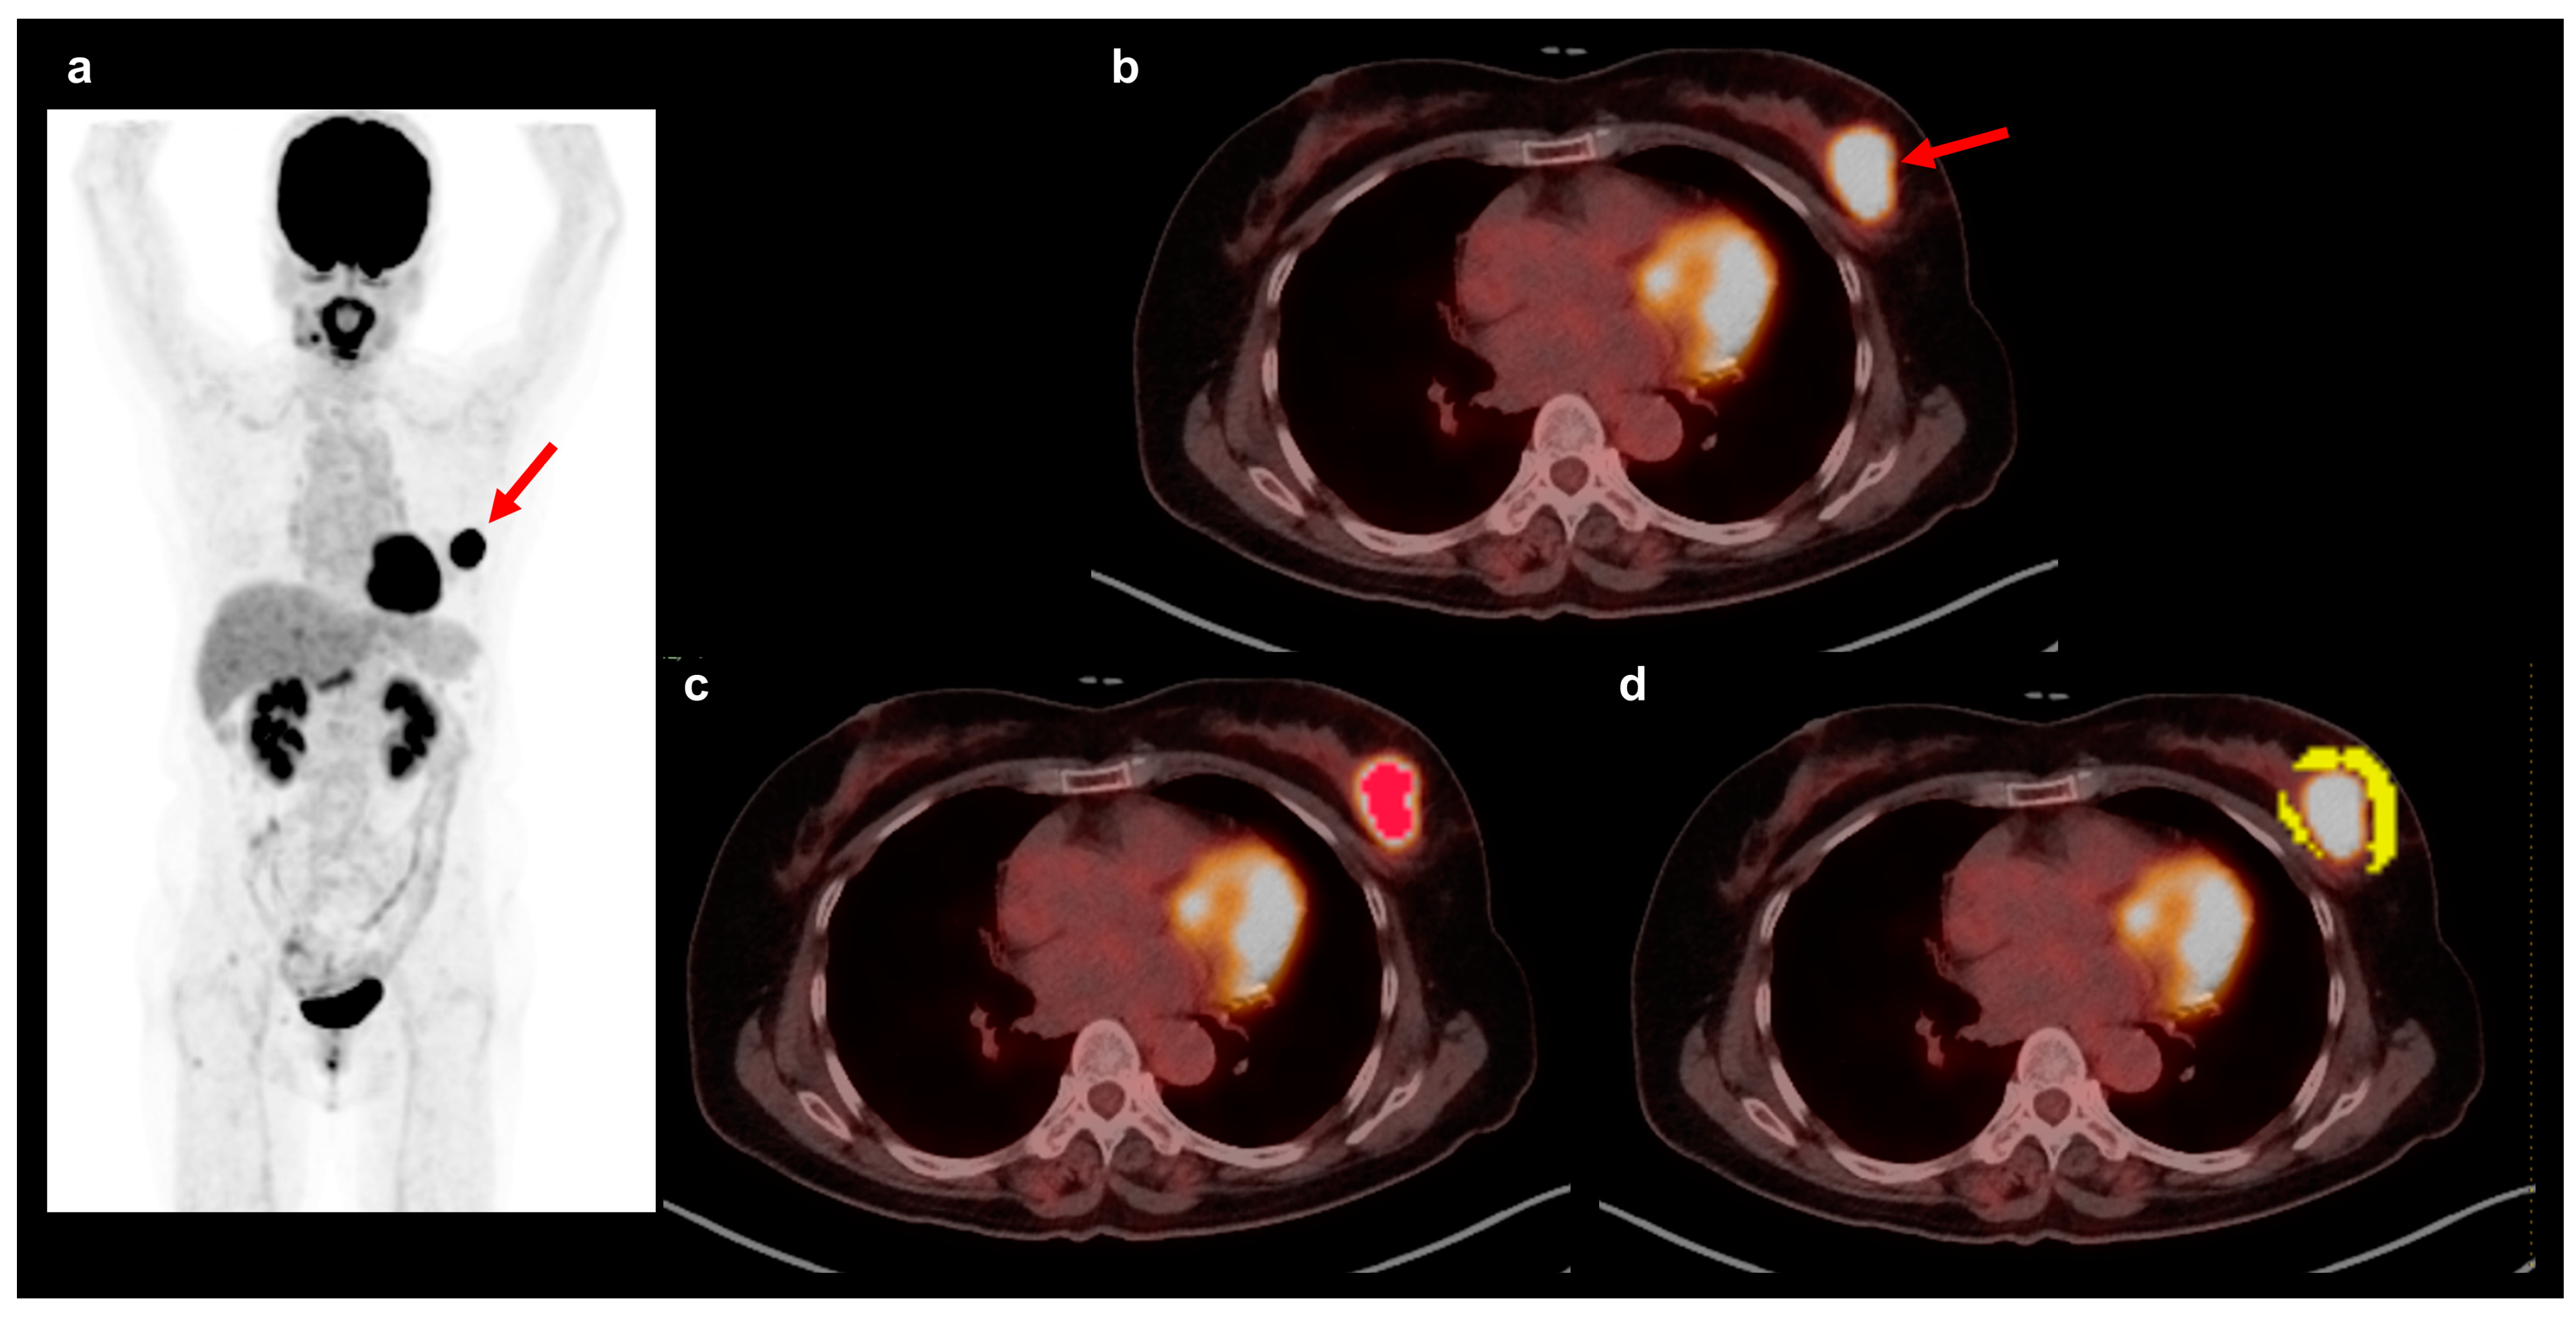

2.3. FDG PET/CT and Textural Analysis